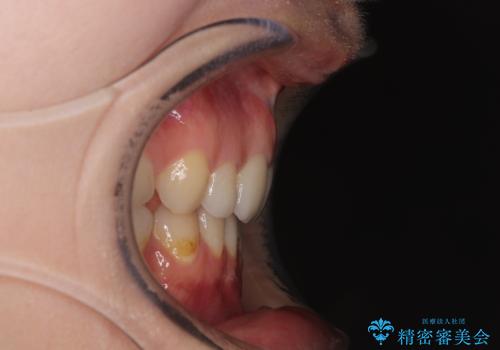

乳歯を残し、欠損部位のスペースを適正な幅に拡大し、インプラント補綴治療により歯列を整える治療も考えられましたが、ご本人から飛び出している前歯をどうしても引っ込めたいとの要望があったため、残存乳歯ならびに上顎左右第二小臼歯を抜歯して、歯列を整えることとしました。

上下臼歯の咬み合わせ改善には補助装置を、深い咬み合わせ改善にはユーティリティーアーチを活用し、ワイヤー装置にて矯正治療を行うこととしました。